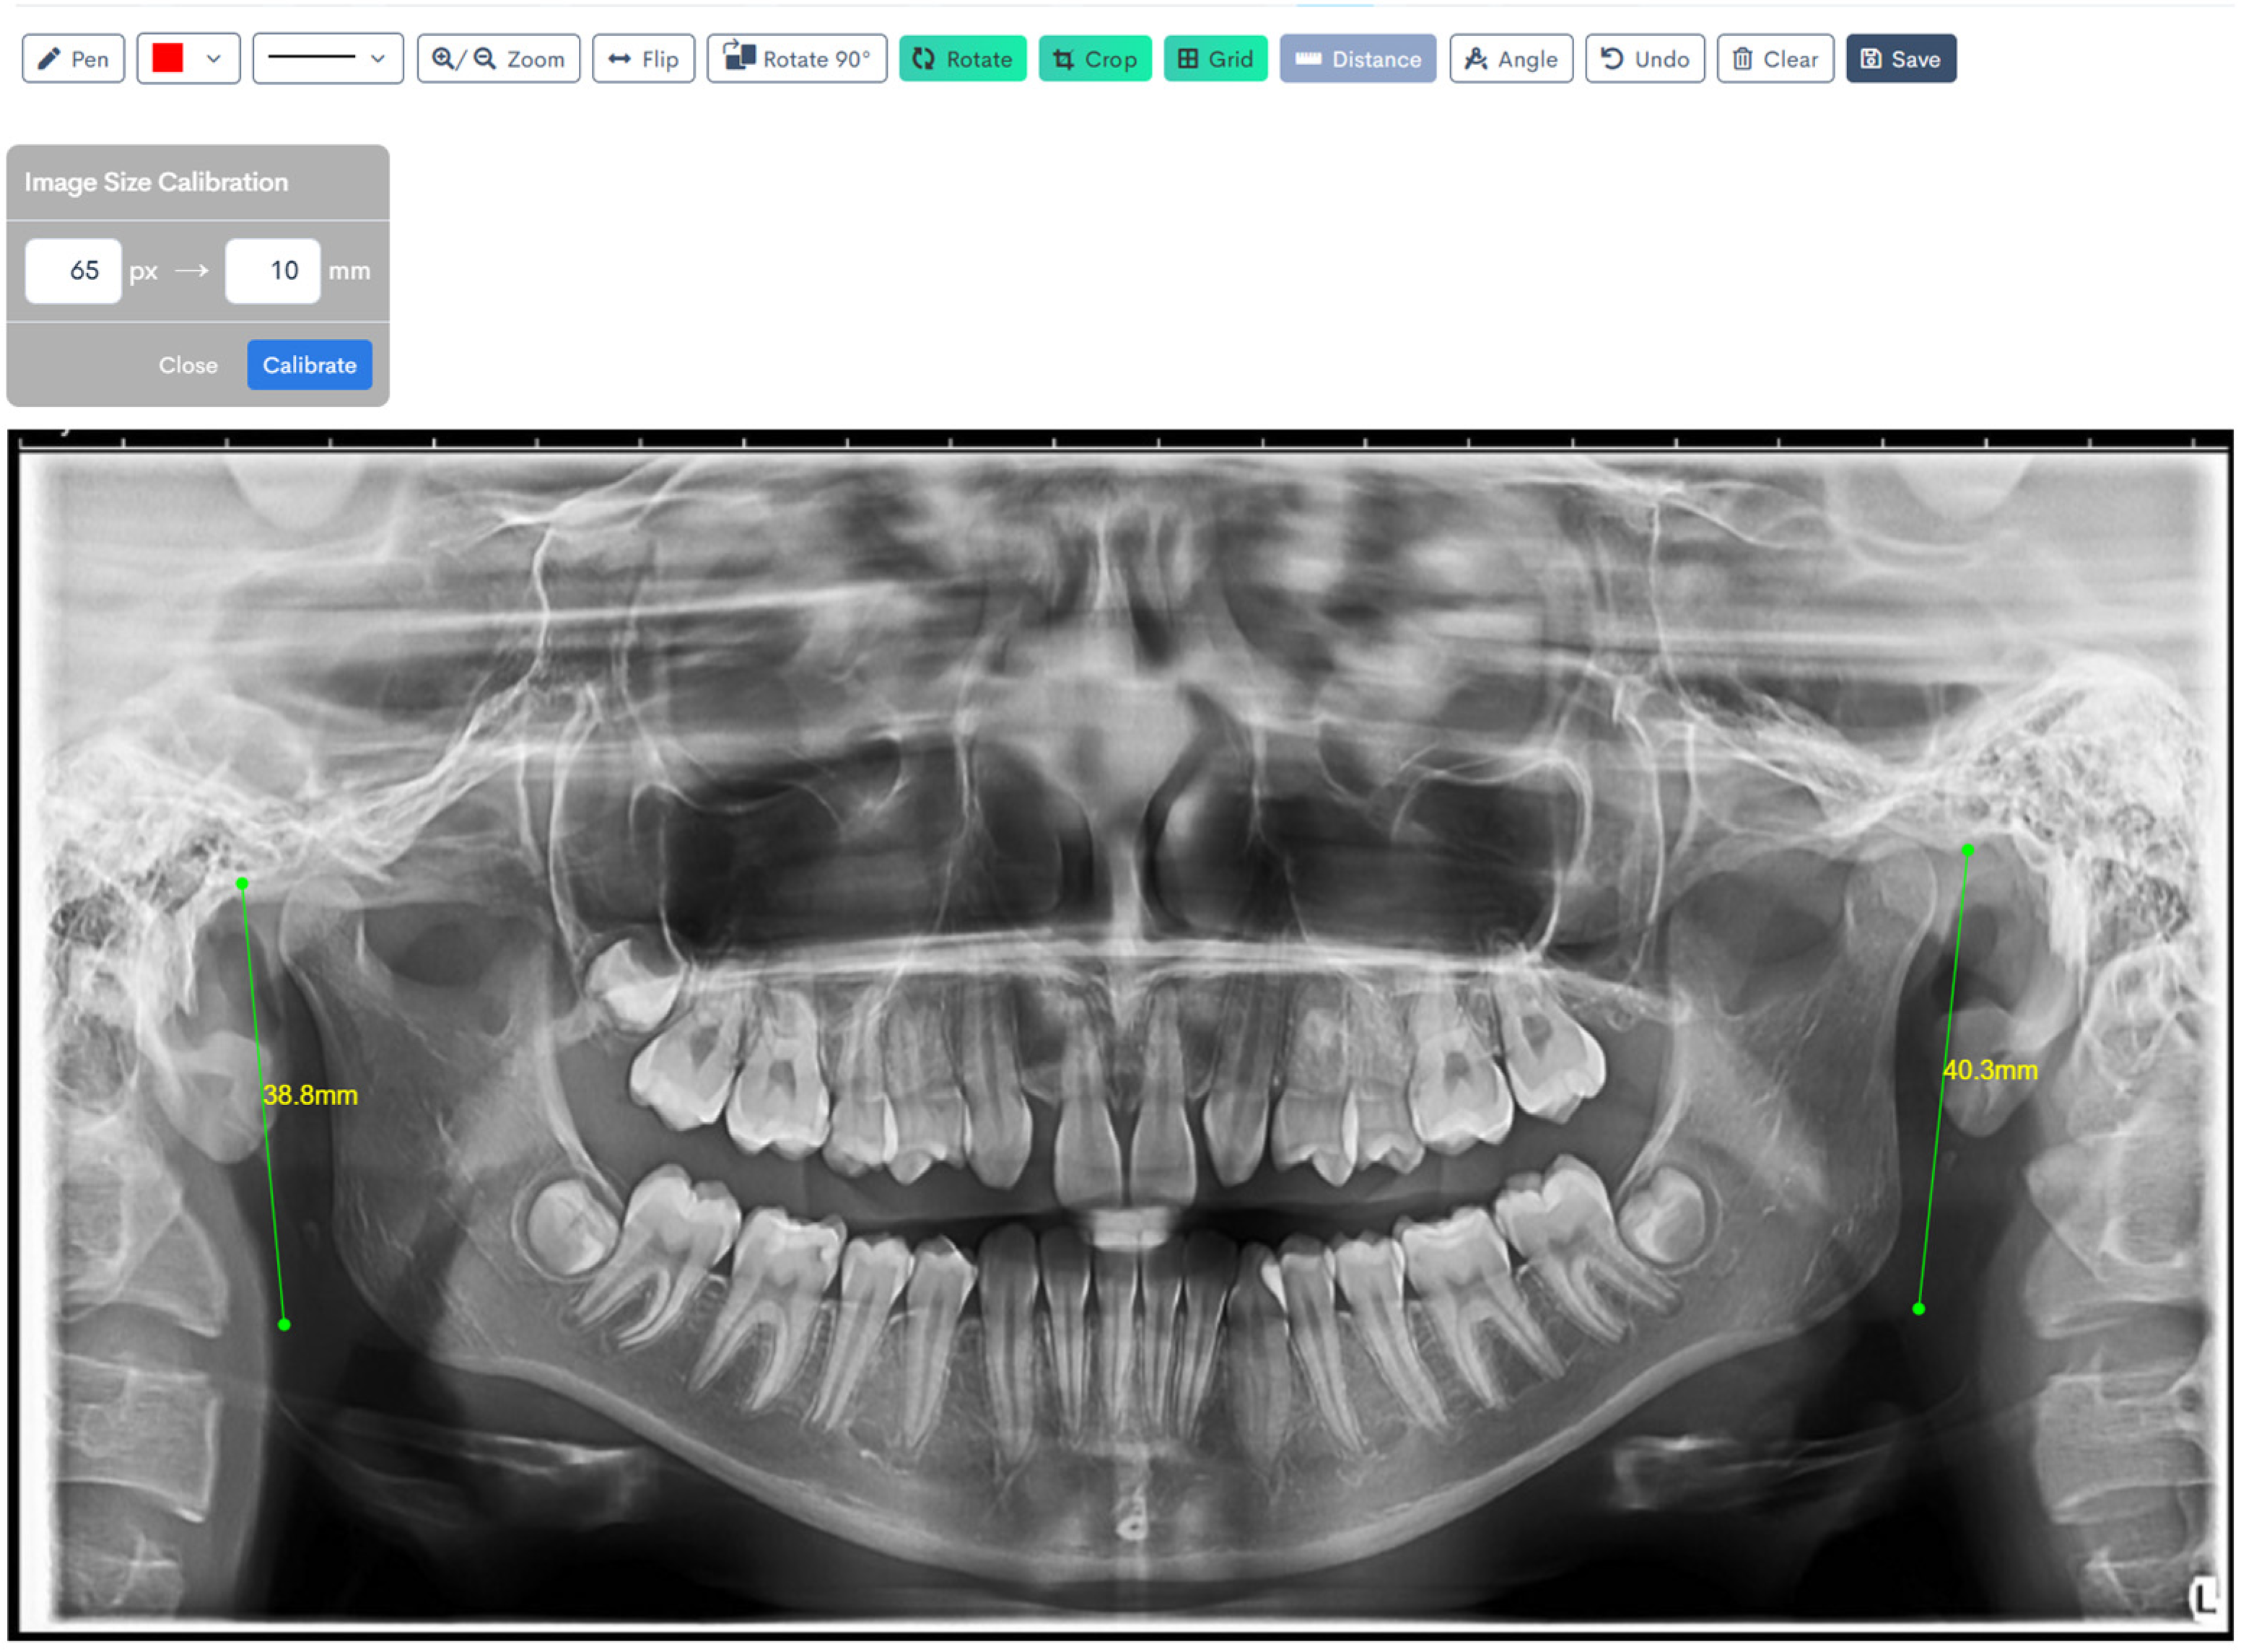

Figure 1, Figure 2, Figure 3, Figure 4, Figure 5 and Figure 6 illustrate the AI-assisted digital measurements exported from the WebCeph software, showing the identification of anatomical landmarks and linear or angular dimensions analyzed in this study.

Orthopantomogram illustrating the measurement of right and left mandibular ramus heights. The ramus height was defined as the linear distance from the most superior point of the mandibular condyle to the lowest point on the inferior border of the mandible, shown by the green lines. Measurements were recorded bilaterally for comparative analysis (Figure 3).

Digital tracing of bilateral ramus heights performed on WebCeph using a panoramic radiograph. Ramus height was defined as the linear distance from the most superior point on the mandibular condyle to the most inferior point on the mandibular border. The left ramus height measured 38.8 mm, and the right ramus height measured 40.3 mm, as shown by the green lines with on-screen readouts (Figure 6).

Figure 3. Bilateral Ramus Height Measurement on OPG. Co (condylion)—the most superior point on the mandibular condyle; Inf—the most inferior point on the mandibular border. The green line (Co–Inf) denotes ramus height measured bilaterally for comparative analysis. Note: Images represent direct screenshots exported from the WebCeph® AI platform. Landmarks and measurement lines were automatically generated and manually verified by the authors.

Figure 6. Digital Tracing of Bilateral Ramus Heights in WebCeph. Co (condylion)—the most superior point on the mandibular condyle; Inf—the most inferior point on the mandibular border. Ramus height (Co–Inf) is represented by the green lines with on-screen readouts (left: 38.8 mm; right: 40.3 mm), illustrating bilateral measurement and comparison. Note: Images represent direct screenshots exported from the WebCeph AI platform. Landmarks and measurement lines were automatically generated and manually verified by the authors.